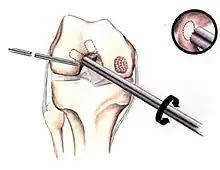

The articular cartilage along the border of the osteochondritis dissecans lesion

Arthroscopic image of OATS surgery on the medial femoral condyle of the knee

If non-surgical measures are unsuccessful, drilling may be considered to stimulate healing of the subchondral bone. Arthroscopic drilling may be performed by using an antegrade (from the front) approach from the joint space through the articular cartilage, or by using a retrograde (from behind) approach through the bone outside of the joint to avoid penetration of the articular cartilage. This has proven successful with positive results at one-year follow-up with antegrade drilling in nine out of eleven teenagers with the juvenile form of OCD,[53] and in 18 of 20 skeletally immature people (follow-up of five years) who had failed prior conservative programs.[54]